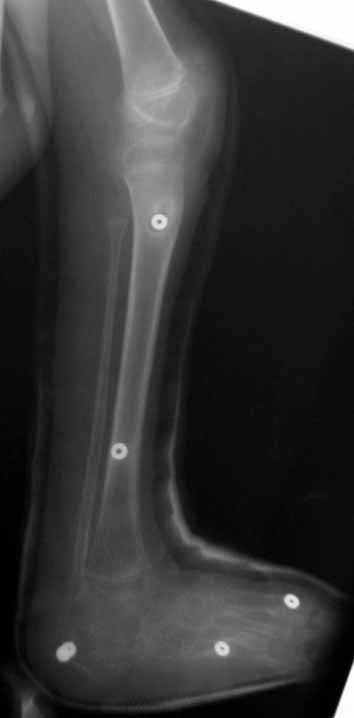

Complex foot deformities can ocur after trauma, neglected or relapsed clubfoot, poliomyelitis, osteomyelitis, burn contracture, neuromuscular diseaes and similar disorders. When treating this deformity with wide soft tissue releases, osteotomies and arthrodesis, there are disadvantages such as the risk of neurovascular injury, soft tissue problems and shortening of the foot. Besides, treating previously operated cases is even harder.

The aim of treatment in foot deformities is to acquire painless and fuctional foot which is plantigrade and at normal size. With the Ilizarov method, correction is planned in 3 planes and performed at a rate depending on the type and degree of the deformity. The deformity is corrected without shortening of the foot, with minimal surgical morbidity and the rate and direction of correction is controlled by the surgeon.

Using the Ilizarov method, foot deformities can be corrected either with or without osteotomy. The system without osteotomy corrects deformities through joints. This technique can be used in patients smaller than 8 years of age and without fixed bony deformity. For patients older than 8 years of age with fixed bony deformity and patients with neuromuscular diseases, in whom maintaining soft tissue correction is very hard, osteotomy is required.